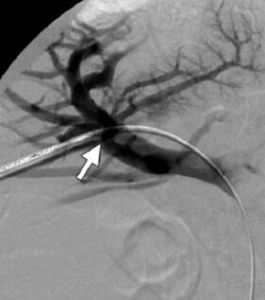

醫源性膽管損傷是指外科手術時意外的造成膽管損傷,通常是肝外膽管的損傷。主要見於膽道手術,尤其是膽囊切除術,此外胃大部切除術、肝破裂修補術、肝切除術時也可...

概述 《流行病學詞典》中的解釋 影響因素 病原體及傳播途徑 臨床特徵LC醫源性膽管損傷的診斷和處理》為“十一五”國家重點電子出版物出版規劃品種,衛生部醫學CAI課件。 LC膽道損傷可在術中、術後24小時以及術後數日乃至數...